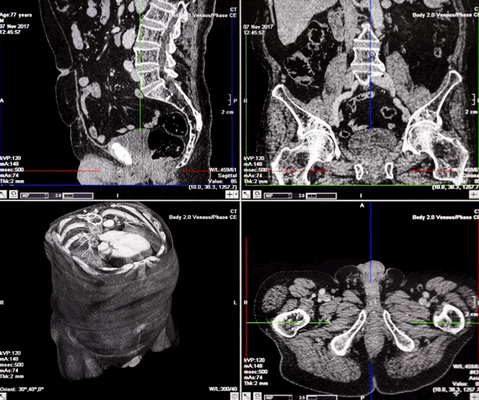

КТ в разных проекциях показывает опухоль в левой почке (стрелка)